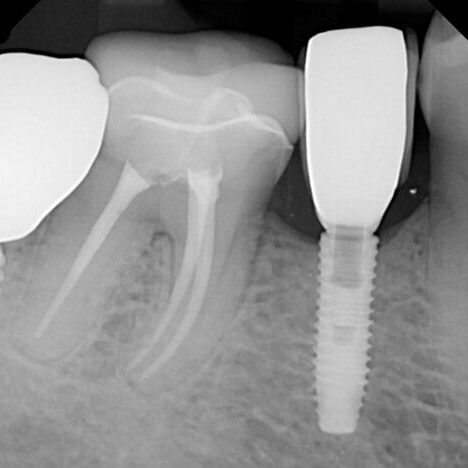

ULTRASONICS: Complications of Abutment Screw Retrieval Secondary to Prior Ultrasonic Attempts

There has been much written on the use of ultrasonics in retrieving fractured screw fragments, which I didn’t think a lot about until May of 2023, as it has not been a part of my fractured screw retrieval algorithm.